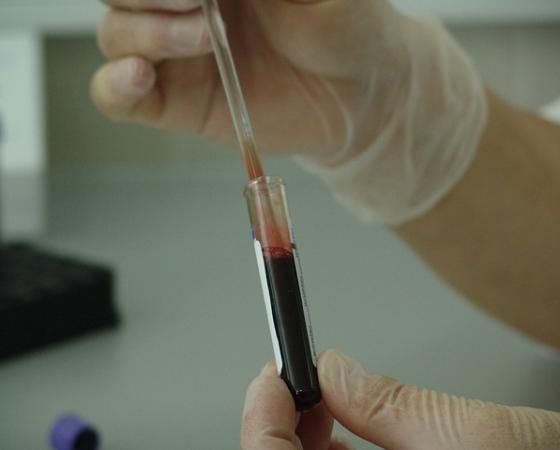

8 Types of Cancer Treatments

8 Types of Cancer Treatments currently used in medical world. Get knowledge on Types of Cancer Treatments, care for your body, don’t overuse it, be smart, eat smart. Daily news…

Food Fighting Cancer Cells | How Does Cancer Develop

Food fighting cancer cells are Apples, Berries, Cruciferous vegetables, Carrots, Fatty fish, Walnuts, Legumes, Supplements, and medications. Cancer is a condition where certain cells in the body grow uncontrollably and…